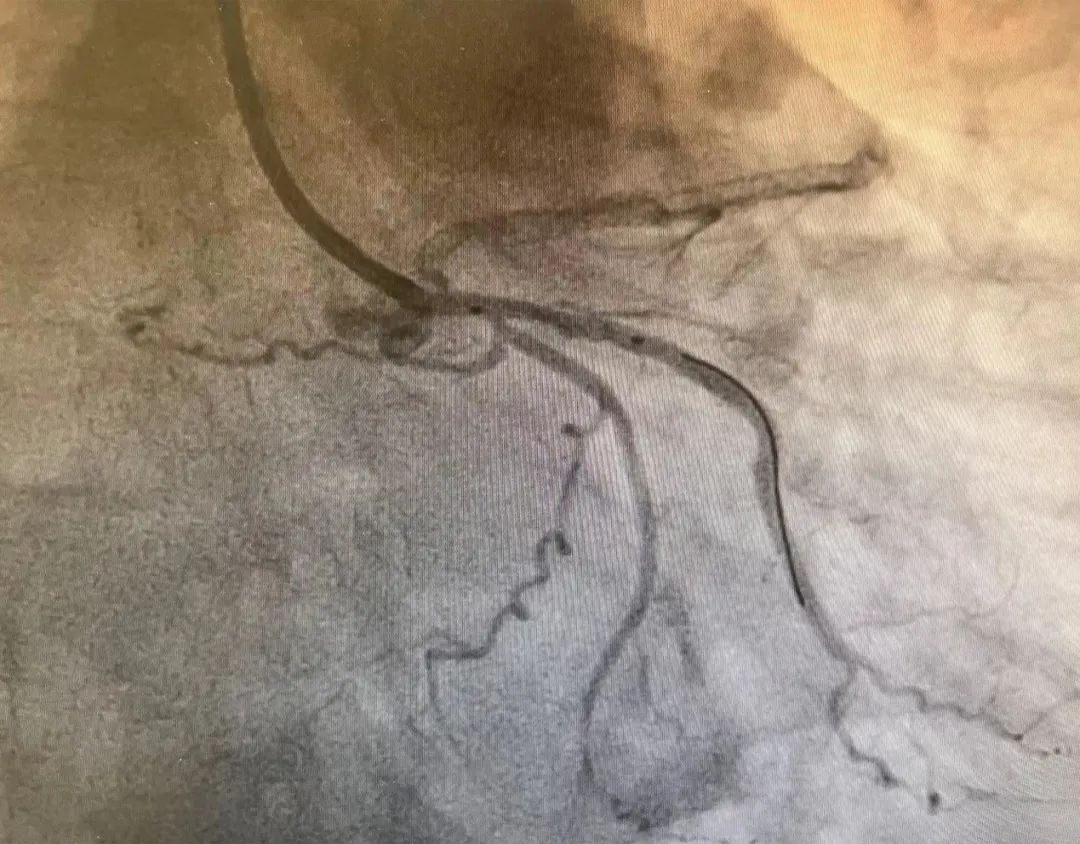

▲患者术前片子

经相关辅助检查发现,患者邹阿姨多处心血管狭窄达90%-100%,属于不能耐受长期双联抗血小板治疗的高出血风险(HBR)患者。心血管内科主任李伟扬带领团队反复论证相关治疗方法,全面评估手术治疗风险,决定由赵智敏副主任主刀为患者实施冠脉造影术及无聚合物药物涂层支架植入术。